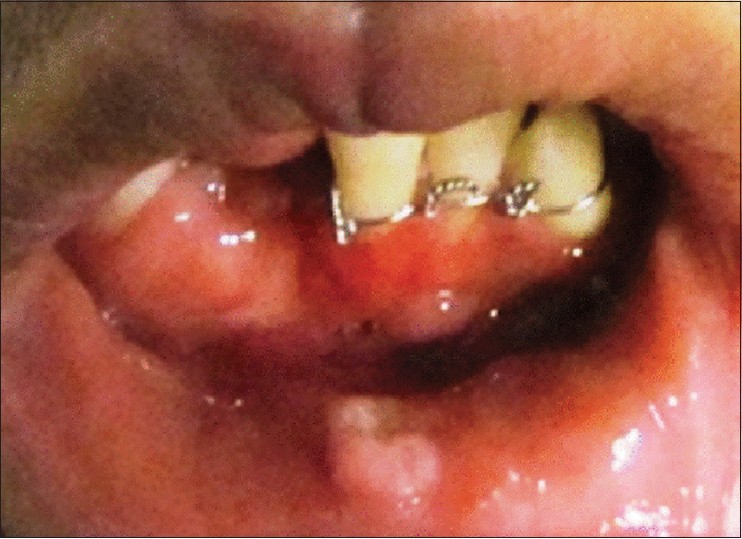

In the extraoral examination, abrasions of the nose, lips, and mentum were present. In addition, the right mandibular incisors had been avulsed. Moreover, silk suture in the lower labial vestibule, from unsuccessful attempts to repair severed mucosa, was noted. Furthermore, debris, necrotic tissue, and exposed bone were present in the vestibular depth [Figure 1]. | Figure 1: Complete mandibular degloving injury exposing mandibular bone from marginal bone to inferior border

Click here to view |